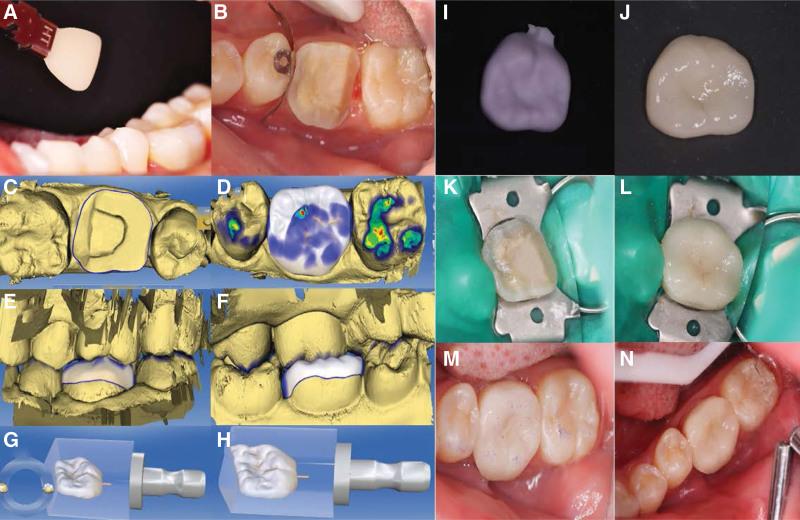

This article presents the clinical report and successful root canal treatment of a 24-year-old healthy female patient with an extensive periapical lesion in a 6-canal first mandibular molar. The patient was admitted to the endodontic department because of a periapical abscess found 1 month ago in her left mandibular first molar.

Chronic apical periodontitis was diagnosed based on clinical examination coupled with radiographic and cone-beam computed tomography images.

The treatment plan was to first perform root canal therapy and then perform clinical observation.

During 1-year follow-up period, the treated tooth was asymptomatic, and complete resolution of the extensive apical lesion was eventually achieved, as shown in the postoperative cone-beam computed tomography images and clinical examination.

The present case emphasizes the importance of a comprehensive understanding of root canal morphology, especially rare anatomical variations, to ensure successful root canal treatment. Additionally, the case report adds to the library of previously reported cases of extensive periapical lesions with a direct connection to the root canal system, which demonstrates the potential clinical advantages of root canal therapy as a conservative nonsurgical approach in these cases.